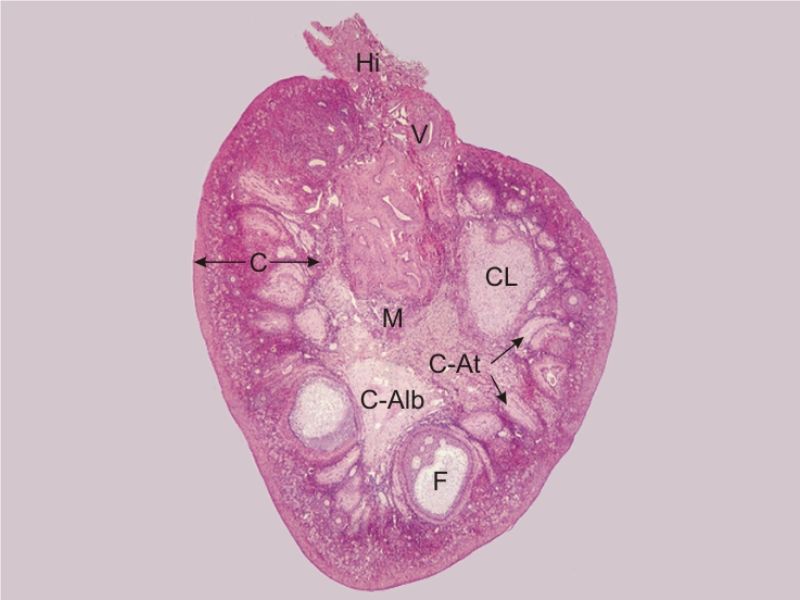

Ovaries

Slide 24

Section of the ovary

1. Outer covering. 1'. Attached border. 2. Central stroma. 3. Peripheral stroma. 4. Bloodvessels. 5. Vesicular follicles in their earliest stage. 6, 7, 8. More advanced follicles. 9. An almost mature follicle. 9'. Follicle from which the ovum has escaped. 10. Corpus luteum.

Ovary

- Capsule covered by modification of peritoneum

- Called germinal epithelium

- Simple squamous/cuboidal

- Subdivided

- Not clearly defined

- Cortex - contains ovarian follicles

- Medulla - vascular

Germinal epithelium

- Misnomer

- NOT source of primary follicles

- Cover capsule

- Simple squamous/cuboidal epithelium

Cortex

- Tunica albuginea

- Irregular dense CT capsule

- Follicles in various phases

- Stroma containing follicles

Stroma

- Highly cellular loose CT

- Fibroblasts

- Elastic & collagen fibres

- Form layers around follicles

Medulla

- Blood vessels

- Hilus cells

- Stroma

Blood vessels

- Enter medulla at hilus

- Supply the cortex

- Epithelioid cells clump around blood vessels

Epithelioid cells

- Located in hilus

- Also called hilus cells

- Clump around blood vessels

- ≈ Leydig cells

- Probably produces androgens

Corpus luteum

Slide 91

Corpus luteum

- Two major cell types

- Granulosa lutein cells

- modified granulosa cells

- Theca lutein cells

- modified theca interna cells

- Many capillaries

Granulosa lutein cells

- Modified granulosa cells

- Large - 30µm

- Pale cells

Theca lutein cells

- Modified theca interna cells

- Smaller - 15µm

- Dark stained